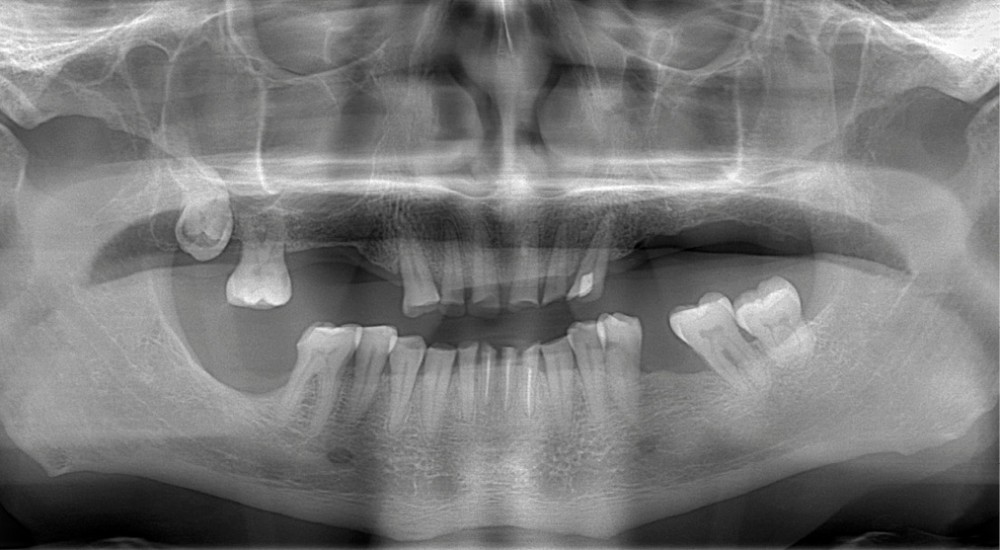

• L’examen intrabuccal montre de nombreux édentements non compensés (14, 15, 16, 24, 25, 26, 27, 47 et 36) ainsi que des pertes de substance très importantes, notamment dans le secteur antérieur.

Une attrition sévère, couplée à une occlusion sans calage postérieur, a engendré des difficultés pour s’alimenter.